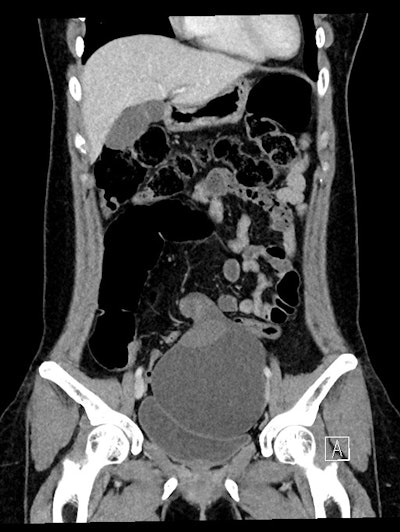

CT coronal; 37-year-old woman -- a large cystic mass in the anterior mid pelvis with smooth hyperdense borders. It converges to the right at a focal area of vascular twisting (whirlpool sign).

Large ovarian cystic masses were present in both cases; the authors underscored that these are a known risk factor for ovarian torsion, and thus an important finding for diagnosis.

In the first case presented, CT showed a large right-sided adnexal cystic mass with evidence of a twisted vascular pedicle referred to as the “whirlpool sign,” suggestive of ovarian torsion. CT in the second case also showed a large lesion, which appeared to originate from a left-sided pedicle.